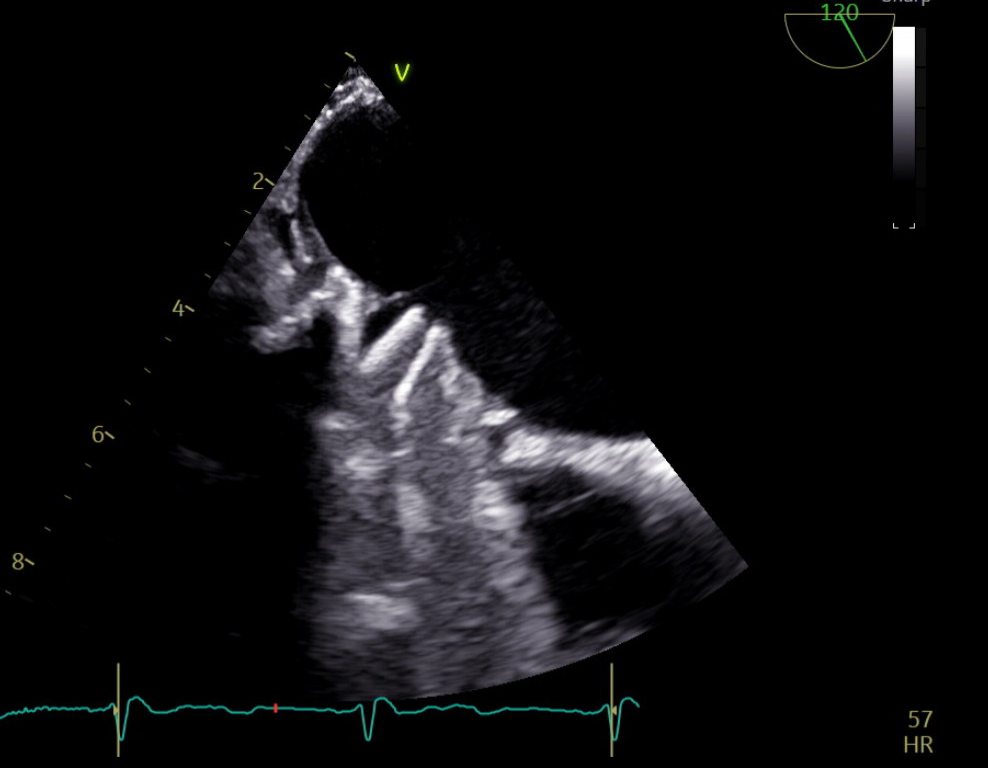

A 47-year-old female with history of thrombophilia (PAI-1 4G/4G genotype), Barlow syndrome with native leaflet repair then mechanical mitral valve (MV) replacement on warfarin, and previous stroke due to MV thromboembolism, presented with more than 24-hour onset of expressive aphasia. CT head showed showed acute ischemic stroke (AIS) in left parietal lobe with left middle cerebral artery (MCA) distal occlusion on CTA-head despite warfarin use and therapeutic INR-2.5. Within hours of admission, she had neurological deterioration and brain MRI demonstrated new left frontal-temporal intracranial hemorrhage (ICH) with cerebral herniation. She emergently received 4F-PCC/vitamin K, underwent decompression craniectomy. TTE showed MV severe stenosis. TEE (Figure 1) confirmed MV thrombus, similar embolic mechanism to prior AIS. To balance the concomitant high risks of strokes given mechanical MV thrombus requiring uninterrupted anticoagulation (AC) and ICH recurrence with AC, she was started on low-dose heparin infusion without bolus day 8. Transcranial Doppler (TCD) (Figure 2) was utilized to determine risk of cerebral embolization from MV thrombus via detection of microemboli or high-intensity transient signals (HITS) within bilateral MCA. Although patient anticoagulated with heparin, we detected 16 HITS in 15 mins of embolic monitoring suggesting high risk of recurrent ischemic stroke. AC was switched to enoxaparin at 1mg/kg twice daily and repeated TCD-emboli on day 15 showed continued AIS risk with 11 HITS even with a therapeutic anti-Xa level of 0.7 (goal 0.6-1.0). Enoxaparin dosage increased guided by emboli monitoring until HITS resolved. She was discharged to stroke rehab with plan to bridge to warfarin (INR goal 3.5-4.0) after 4 week. At one-month follow-up, she remained on warfarin 10mg daily with therapeutic INR and free of recurrent AIS or ICH.